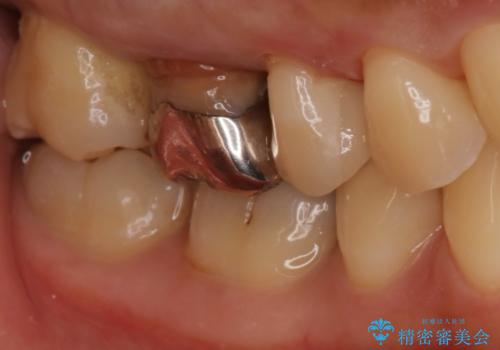

- 右上4、5の歯がしみるのを治したいという主訴で来院されました。精査の結果隣接面う蝕と診断し、適合がよく見ためも良いセラミックインレーでの治療を行いました。

セラミックインレーを入れた後は歯がしみることはなくなり、白く丈夫な被せ物が入り満足いただけました。